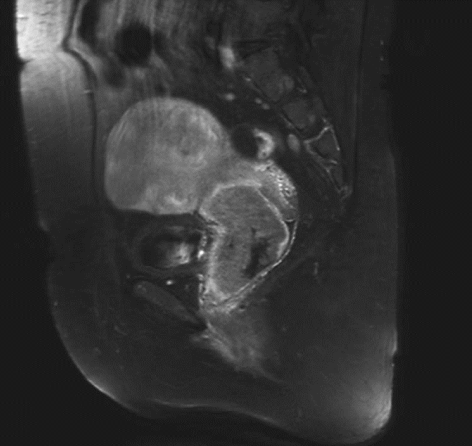

ⅠB1期宫颈癌MR ⅠB2期宫颈癌MR

ⅡA1期宫颈癌MR ⅡA2期宫颈癌MR

ⅡB期宫颈癌MR ⅢA期宫颈癌MR

ⅢB期宫颈癌MR ⅣB期宫颈癌MR